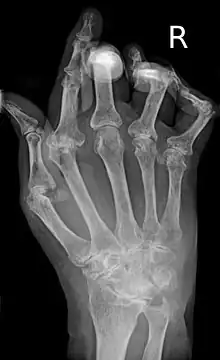

| A hand severely affected by rheumatoid arthritis. This degree of swelling and deformation does not typically occur with current treatment. | |

As the pathology progresses the inflammatory activity leads to tendon tethering and erosion and destruction of the joint surface, which impairs range of movement and leads to deformity. The fingers may develop almost any deformity depending on which joints are most involved. Specific deformities, which also occur in osteoarthritis, include ulnar deviation, boutonniere deformity (also "buttonhole deformity", flexion of proximal interphalangeal joint and extension of distal interphalangeal joint of the hand), swan neck deformity (hyperextension at proximal interphalangeal joint and flexion at distal interphalangeal joint) and "Z-thumb." "Z-thumb" or "Z-deformity" consists of hyperextension of the interphalangeal joint, fixed flexion and subluxation of the metacarpophalangeal joint and gives a "Z" appearance to the thumb.[16]: 1098 The hammer toe deformity may be seen. In the worst case, joints are known as arthritis mutilans due to the mutilating nature of the deformities.[20]